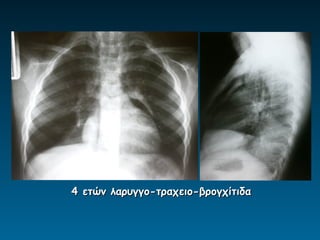

4 ετών λαρυγγο-τραχειο-βρογχίτιδα